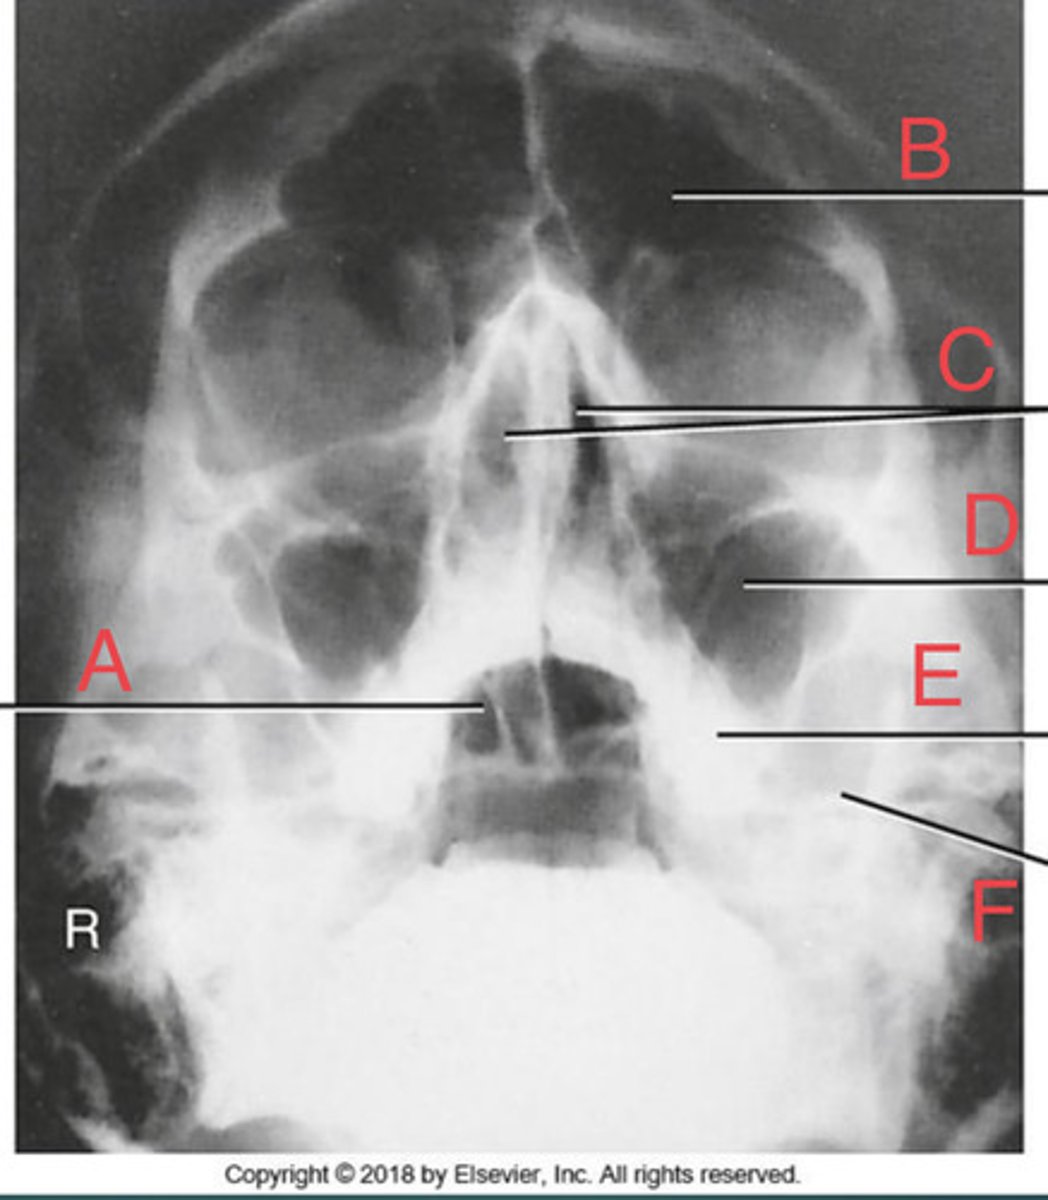

PA Caldwell Sinuses

What position?

frontal sinus of the frontal bone

A.

R. ethmoid sinus of the ethmoid bone

B.

crista galli of ethmoid bone

C.

L superior orbital fissure of the sphenoid

D.